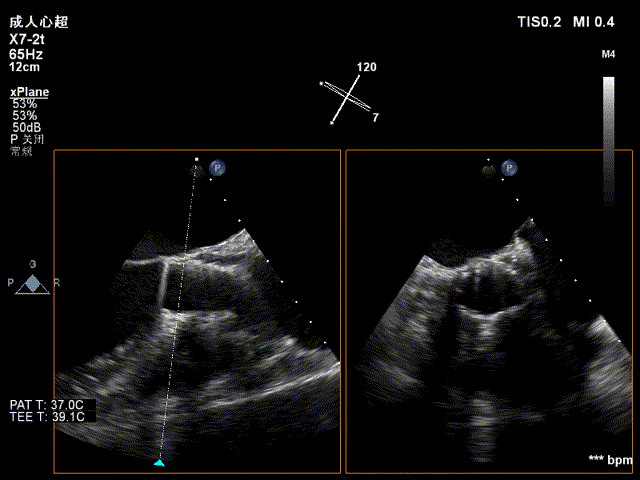

超声看左冠窦侧6mm左右

完全释放,无反流

超声看完全释放下滑至7mm

几乎无反流

几乎无瓣周漏

观察后无下滑